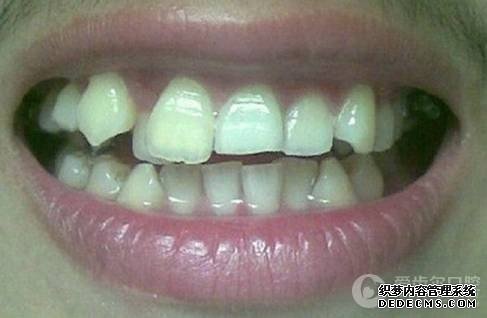

患者自述:眼看快到而立之年,身边好友都已成家立业,可我依然孤身一人,难免有些落寞。可是因为牙齿不齐,让我总是缺乏自信,性格也变得内向腼腆,几次相亲都被心仪的女孩拒绝。为了不被自卑心吞噬,我决定通过牙齿正畸改变自己,给自己一次幸福的机会。

临床诊断:通过3D数字化全景机的拍片检查,患者上下牙排列拥挤,前牙受挤压向内歪斜,咬合关系异常,唇形尚可,颞下颌关节检查未见异常,无蛀牙、牙周疾病症状。经过和患者商量,选定自锁托槽矫正方案,调整牙间隙,恢复牙齿的正常排列,实现正常的咬合关系。

矫正前旧照